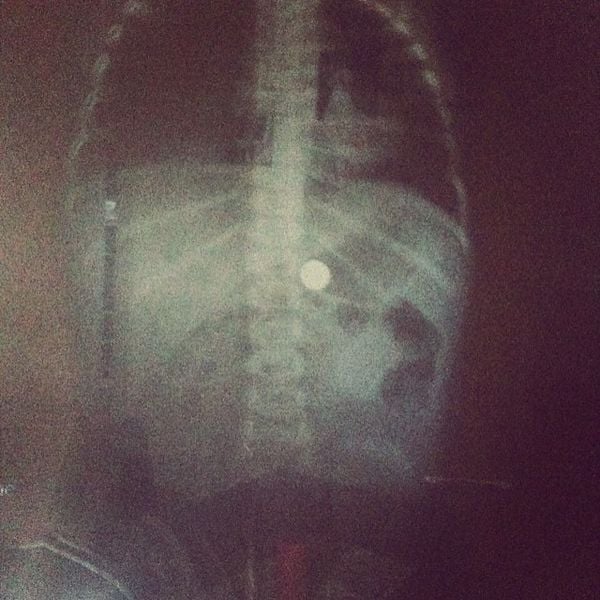

TWO weeks ago, Brooke O’Connor opened a package she purchased online to the horror of a button battery falling onto her living room floor. “Button batteries are hiding everywhere whether it is in grandpa’s hearing aids or a musical greeting card – they are there, and they are scary,” she told The Guardian. The Swan […]